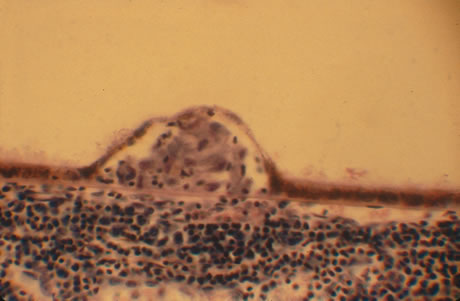

In primary ocular HSV infections, a severe follicular conjunctivitis with regional adenopathy is present. Vesicles may appear on the eyelid skin or lid margin, producing blepharitis (Fig. 3). Corneal involvement initially takes the form of a superficial punctate keratitis, which may progress to dendritic or geographic ulceration. Stromal infiltrates and uveitis are less common and relatively mild in primary disease. In uncomplicated cases, lesions usually heal completely in 2 to 3 weeks without scarring. Most cases of ocular HSV are recurrences. Recrudescent ocular herpes may take the form of dendritic or geographic ulcers, recurrent erosions, interstitial or disciform stromal keratitis, and anterior uveitis.3 HSV may also be an agent of retinitis and acute retinal necrosis (Fig. 4).

|